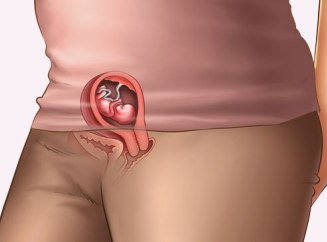

Зачаття дитини може відбутися протягом певних днів циклу жінки. На 11-15 день після першого дня початку менструації яйцеклітина покидає яєчник і ці дні вважаються сприятливими для зачаття. Весь інший час вважається безпечним. але на 100% не можна вважати його таким.

Для того щоб краще розібратися в питаннях настання вагітності, давайте спочатку скажемо кілька слів про жіночої фізіології. Отже, у кожної здорової дівчини овуляція відбувається практично кожного місяця. У ці дні яйцеклітина максимально готова до запліднення. А, отже, ризик завагітніти в ці дні досить високий. Овуляція, як правило, буває в середині циклу і триває кілька днів.